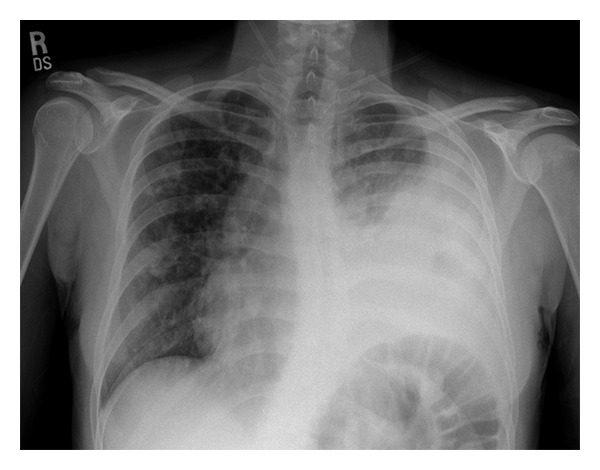

Input 2: What is seen in the X-ray and what should be done?

Image: